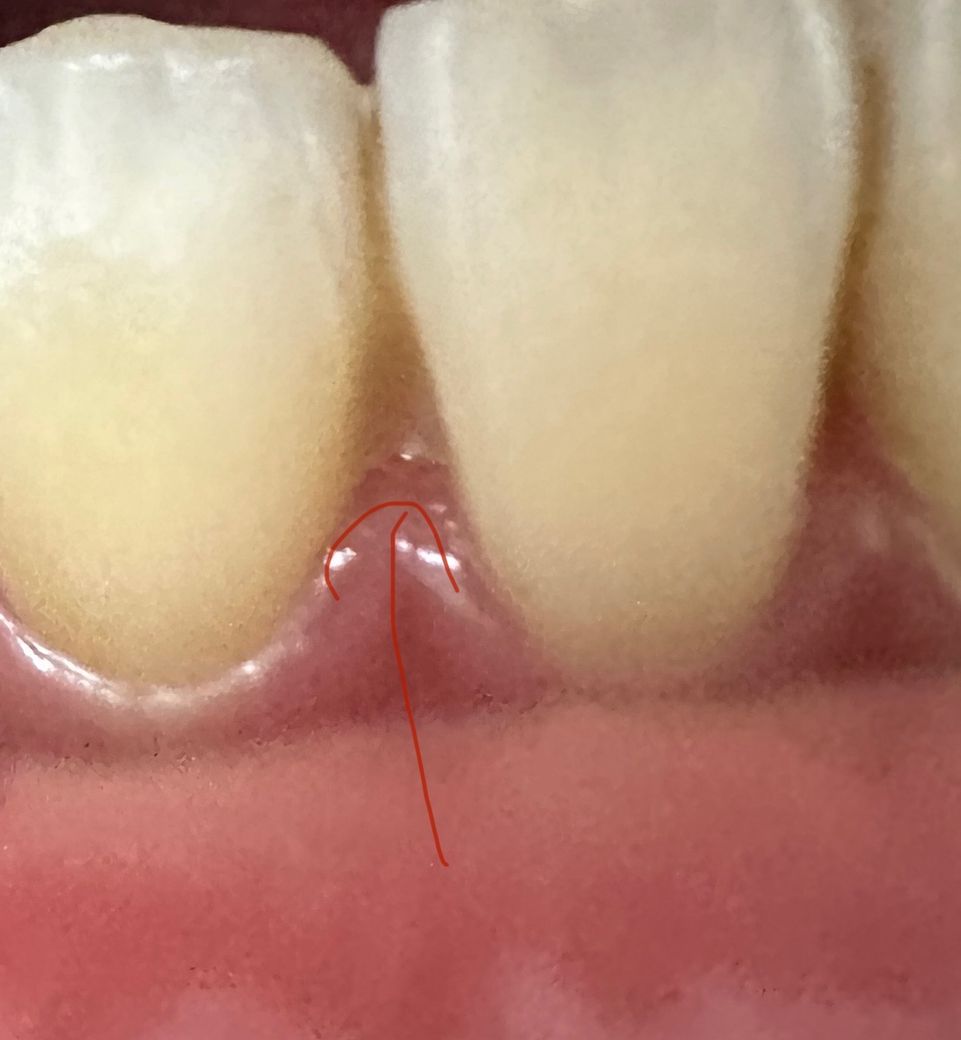

고정식유지장치 재부착했는데 사이가 치실이 안들어가져요

안녕하세요! 오늘 아래 정중앙 앞니 두개중 하나에 유지장치가 벌어져서 몇년전 교정마친 치과에서 재부착을 처음 받았는데 집에와서 양치하려 보니 치실이 안들어가져서 놀래서 거울을 봤는데 잇몸사이로 레진이 보여요.. 이거 원래 이렇게 부착하는건가요..?

• 2번 째 사진

지금 사진으로서는 해당 부분의 레진을 열어주는 것이 좋을 수 있어 보이나 고정유지장치를 낄 당시의 치아 상태에 따라 현재 상태로 레진을 했는 이유가 있을 수도 있어 보입니다. 계속해서 불편감이 있거나 의문이 있다면 교정치과 방문 후 해당 부분에 대한 검사를 해보고 상담을 해보시는 것이 좋아 보입니다.

네 고정식유지장치를 한 상태라면 원래 치아 사이로 치실이 안들어갑니다 치간칫솔이나 워터픽을 쓰셔야 합니다